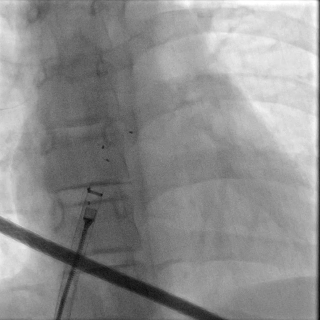

牵拉试验

锁定后,封堵器形态良好,进行牵拉试验,

DSA下可见封堵器整体移动,右盘面未被拉开

释放封堵器

DSA下可见Mark点聚拢